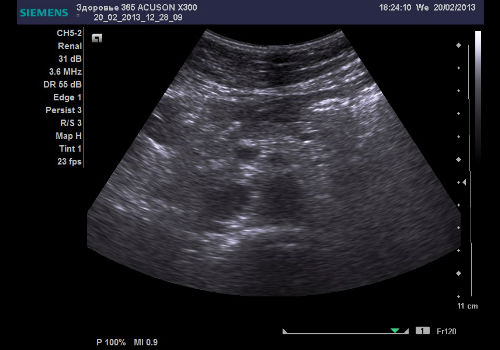

Особый уровень информативности о том, в каком состоянии находится паренхиматозный орган, несет контур поджелудочной железы. У здорового человека он имеет красивые, плавно перетекающие и четкие абрисы. Но, если на ультразвуковой диагностике визуализируются неровные контуры у поджелудочной железы, то можно судить о развитии патологии. Причем, чем неровный контур может иметь расплывчатые границы, шероховатость, либо зазубренный край. А бугристые набухания могут проявляться в не типичных местах, к примеру, в области шейки.

Выявить развитие новообразований раковой этиологии в большинстве случаев довольно сложно, так как чаще всего они визуализируются уже на более поздних стадиях развития. Но, в типичных ситуациях, на мониторе ультразвукового аппарата зачастую можно рассмотреть наличие небольших гипоэхогенных образований, имеющих нечеткие границы, это и является местом расположения опухоли, отека, либо зоны панкреатического поражения.

При развитии кисты, нарушения оттока ферментов, застоя венозного и артериального кровообращения, либо абсцесса, ультразвуковая диагностика выявляет на экран эхонегативные зоны в поджелудочной железе, которые никак не отражают ультразвуковую волну и на экране проявляются в виде пятен белого цвета.

Полностью белая поджелудочная железа может проявляться на мониторе при развитии острой формы панкреатита, который также покажет неровность контуров исследуемого органа, с размытым очертанием. Более того, при панкреатите: структура неоднородная с различной степенью эхогенности на разных участках железы.